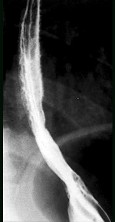

- 单项选择题男,34岁, 胸骨后烧灼痛1周,伴吞咽痛, 餐后平卧时加剧,食管钡餐检查如图, 应诊断为  (    )

- C、反流性食管炎